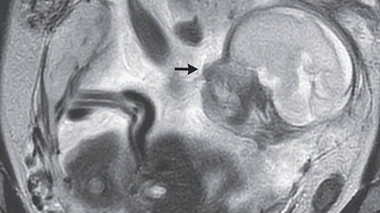

Longueur du col ? Aujourd'hui, on sait mieux évaluer les risques. Par exemple, on sait qu'il ne suffit pas que le col de l'utérus soit dilaté pour que l'accouchement soit imminent, sa longueur est un paramètre plus décisif. En effet, si celle-ci diminue, le risque est réel. Avant, on ne pouvait mesurer manuellement que l'ouverture du col, alors qu'aujourd'hui, l'échographie permet d'en connaître sa longueur.